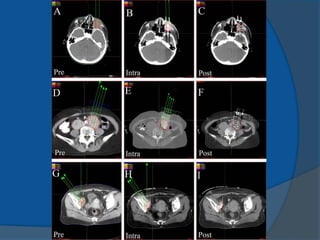

1980 Martinez and colleagues newbrachytherapy approaches to the treatment of prostate cancer were initiated temporary seeds inserted using a transperineal approach Dr Puthawala and colleagues pioneered a temporary seed technique of placing the needles, while visualizing them through an open laparotom Dr Whitmore and colleagues MSKCC began to insert I-125 seeds as a sole treatment through an open incision mid- 1980s transrectal ultrasound-guided, template-guided I-125 implantation procedure has become the primary technique of permanent seed implantation

• 49.

1983 Hans HenrikHolm use of transrectal ultrasound to visualize the permanent placement of I-125 seeds via needles inserted through the perineum directly into the prostate implanting I-125 seeds into cancerous prostates, under the direction of axial imaging from a rectal probe mounted on a sledge-stepper (stepping unit). 1985 Blasko and Ragde the first transperineal, ultrasound- guided approach in the United States ultrasound-guided approach resulted in increased accuracy of needle and seed placement and relatively even distribution of seeds throughout the prostate it allowed computerized treatment planning of the implant rather than the use of simple nomograms ensuring the proper number, strength, and positioning of radioactive sources.